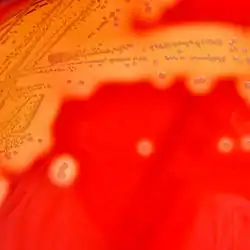

Streptococcus pyogenes або стрептокок групи А (англ. GAS) — аеробна, грам-позитивна бактерія. Нерухомий, не утворює спори, має форму коків завдовжки менше 2 мкм. При розмноженні клітини бактерій утворюють ланцюжки. При вирощуванні на агарі утворюють великі колонії діаметром більше 0,5 мм[1]. Має β-гемолітичну картину росту на кров'яному агарі та налічує понад 60 різних штамів[2][3]. Тест на каталазу — негативний.

_on_Columbia_Horse_Blood_Agar_-_Detail.jpg.webp)